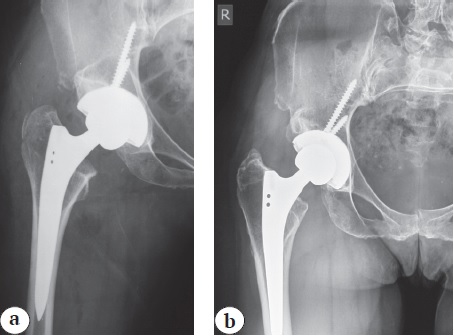

In 49 (15.1%) observations when the Alloclassic femoral stem was used, the presence of radiolucent lines along the stem of the prosthesis, more pronounced in the proximal region, was detected. No such lines were found when using the SL-PLUS MIA stem.

In our study, we could not detect the intensity and localization of radiolucent lines depending on the varus-valgus position of the stem (Table 6).

Other unfavorable variants of bone remodeling are radiolucent lines at the prosthesis-bone interface [22]. Appearance of this phenomenon also depended on the follow-up period, but it was observed only in patients with the Alloclassic stem. Mean follow-up period in the group with the presence of radiolucent lines was 103.5 months in patients with the Alloclassic stem, with a minimum follow-up period of 12 months, and 76.2 months in patients with no radiolucent lines. Mean follow-up period with the SL-PLUS MIA stem was 35.4 months, which is significantly shorter than the mean period with the Alloclassic stem and does not exclude the development of this phenomenon in the future. At the same time, the minimum term at which the lines are detected is 12 months. It is possible that the absence of this phenomenon in the group with the SL-PLUS MIA stems is due to the peculiarities of its design, in particular, the presence of hydroxyapatite coating in the proximal part, especially since the maximum follow-up period of these stems in our study is 60 months. Probable influence of the hydroxyapatite coating in the proximal part of the stems is also confirmed by a comparative study by A. Tanaka et al. in which they found radiolucent lines when using the SL-PLUS MIA stems with hydroxyapatite in comparison with the SL-PLUS MIA stems without hydroxyapatite, in which lucent lines were found in 6% of cases [23]. On the other hand, D. Hoornenborg et al. did not observe a positive effect of hydroxyapatite coating on Zweymüller stems with regard to their possible migration [24, 25].